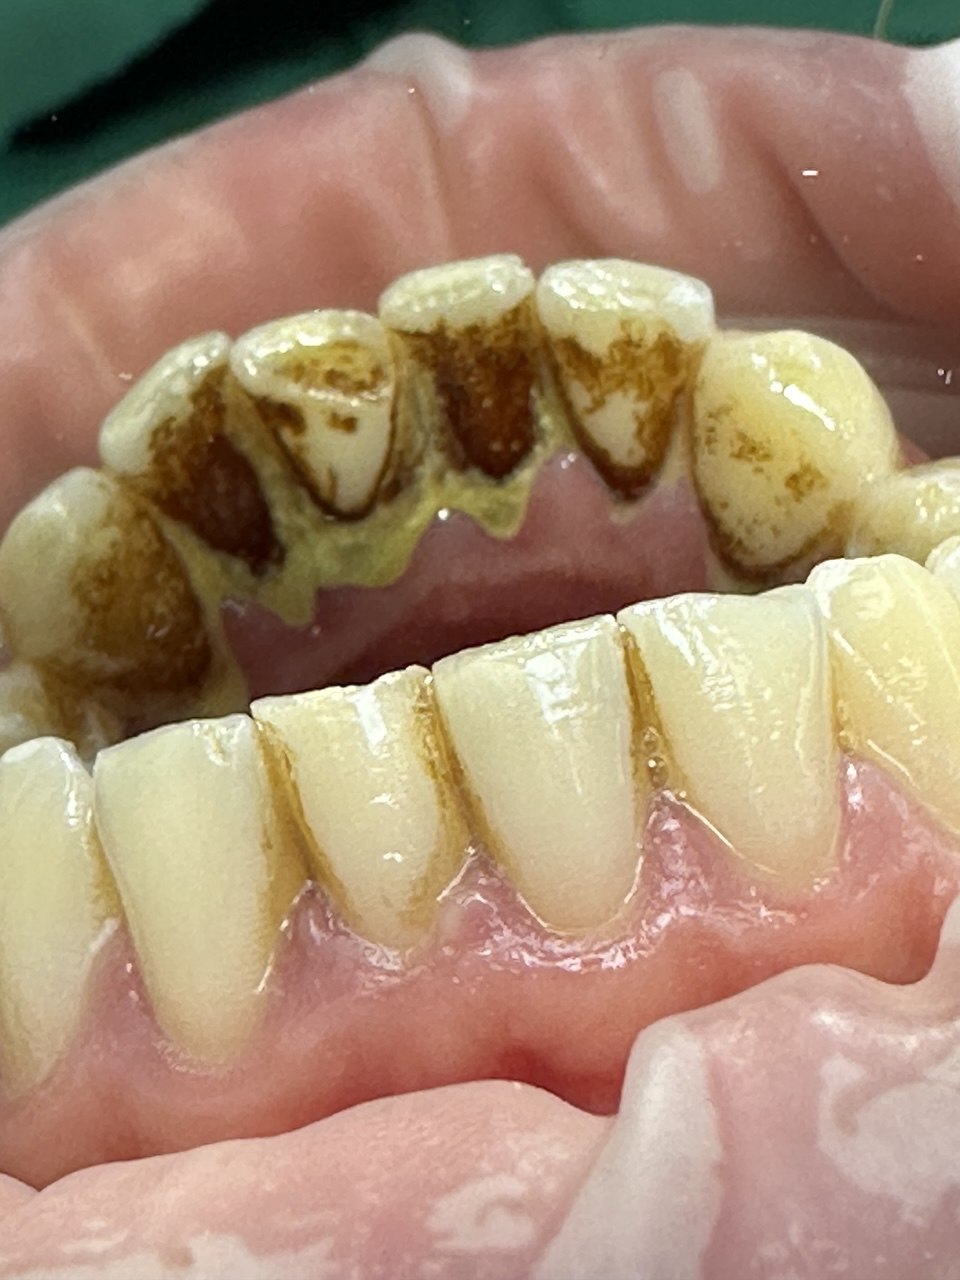

Проблема

У пациента выраженные зубные отложения и пигментированный налёт, особенно в области нижних и верхних передних зубов, с воспалённым краем десны.

Решение

Проведена профессиональная гигиена полости рта — налёт и камень удалены, зубы стали заметно чище и светлее, состояние десны улучшилось.